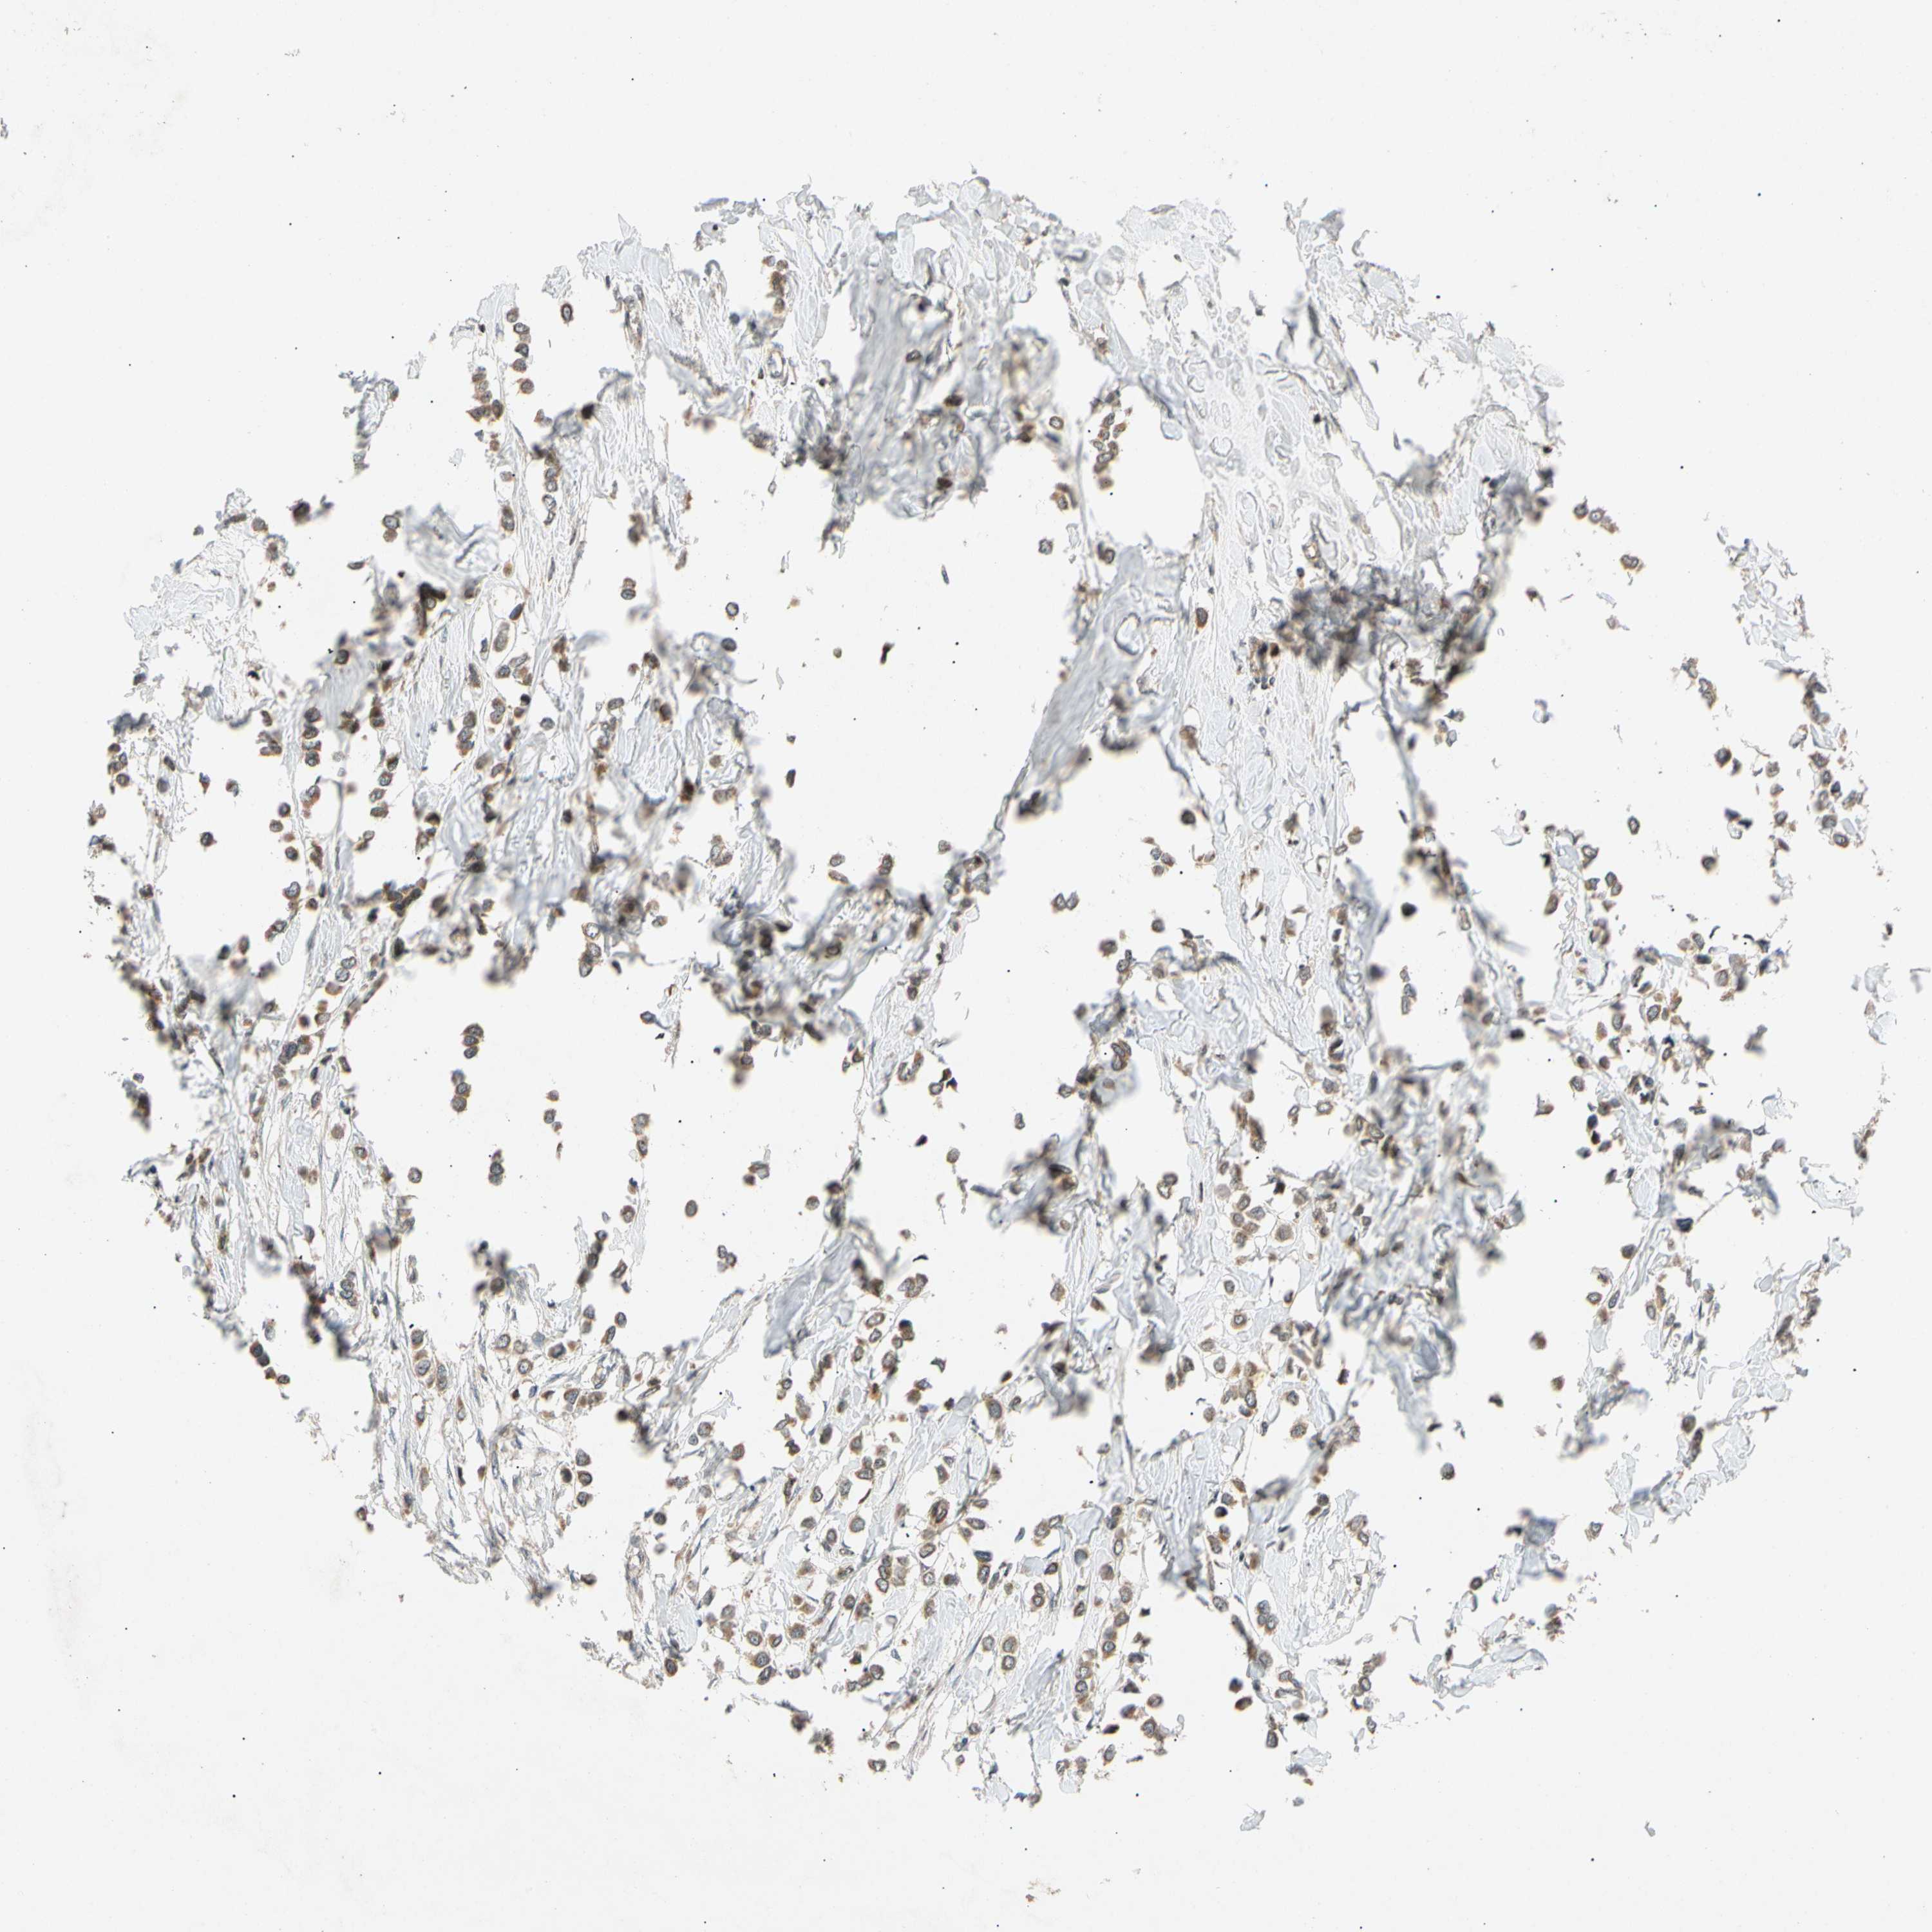

CANCER BREAST CANCER Show tissue menu

BRCA TCGA BRCA VALIDATION PROTEIN EXPRESSION